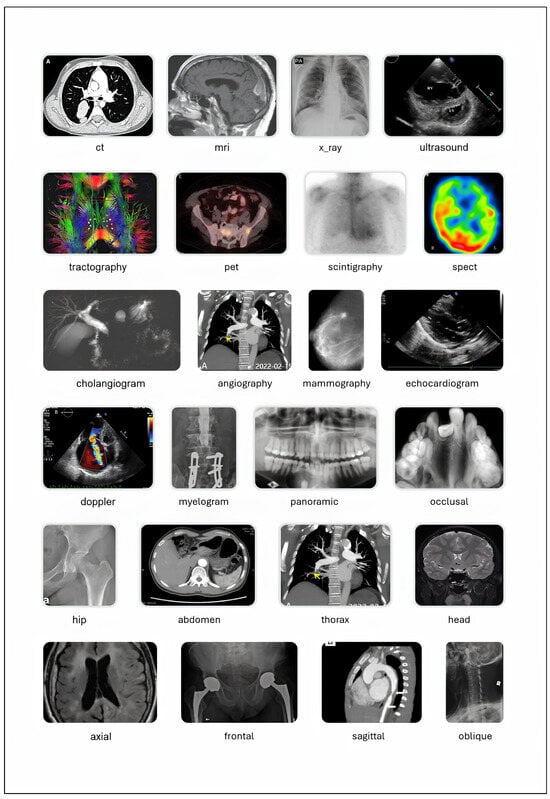

The taxonomy of a classification dataset consists of its classes, their hierarchical relationships, and the logical constraints among them (such as mutual exclusivity). In this version of the dataset, the taxonomy was developed using the previous version as a foundation, considering the terms present in image captions, and referencing different domain ontologies accessed via BioPortal: SNOMED CT, MeSH, the Foundational Model of Anatomy (FMA) and RadLex [43,44,45,46,47]. The structure of the taxonomy follows the principles of the Multiplex Classification Framework, a methodology that enables complex classification problems to be addressed as a set of simpler binary or multiclass tasks, organized either in parallel or sequentially [48]. The full taxonomy was published in Bioportal as MCR_TX, and includes 163 classes (including the root_class, 17 negative classes such as no_doppler, and 145 positive classes) [49]. A reduced version with 81 classes (80 positive ones and the root_class) was developed by excluding the least important ones in order to simplify the training of machine learning (ML) models (see the ML_MCR_TX taxonomy in BioPortal) [50]. Figure 4 displays multiple classes from the MCR_TX taxonomy, each accompanied by an example image. In the MultiCaRe dataset, an image can have multiple associated labels, provided that the logical constraints among them are respected (for more details, refer to the taxonomy documentation available in the GitHub repository).

Figure 4.

Selected classes from the medical image taxonomy. For details on the class structure, please refer to the taxonomy documentation. ‘ct’: Computed Tomography, ‘ekg’: Electrocardiogram, ‘eeg’: Electroencephalogram, ‘fish’: Fluorescence In Situ Hybridization, ‘h&e’: Hematoxylin and Eosin, ‘ihc’: Immunohistochemistry, ‘mri’: Magnetic Resonance Imaging, ‘oct’: Optical Coherence Tomography, ‘pet’: Positron Emission Tomography, ‘spect’: Single Photon Emission Computed Tomography. Image credits: ct [51], mri [52], x_ray [53], ultrasound [54], tractography [55], pet [52], scintigraphy [56], spect [57], cholangiogram [58], angiography [59], mammography [60], echocardiogram [61], doppler [54], myelogram [62], panoramic [63], occlusal [64], hip [65], abdomen [66], thorax [59], head [67], axial [68], frontal [69], sagittal [70], oblique [71]. All images are licensed under CC BY. Selected classes from the medical image taxonomy. Image credits: colonoscopy [72], bronchoscopy [73], gastroscopy [74], cystoscopy [75], h&e [76], masson_trichrome [77], papanicolaou [78], immunofluorescence [79], ihc [80], methylene_blue [81], congo_red [82], gram [83], fish [84], giemsa [85], methenamine_silver [86], chart [87], ekg [88], eeg [89], oral_photograph [90], skin_photograph [91], fundus_photograph [92], ophthalmic_angiography [93], oct [94], slit_lamp_photograph [95]. All images are licensed under CC BY.